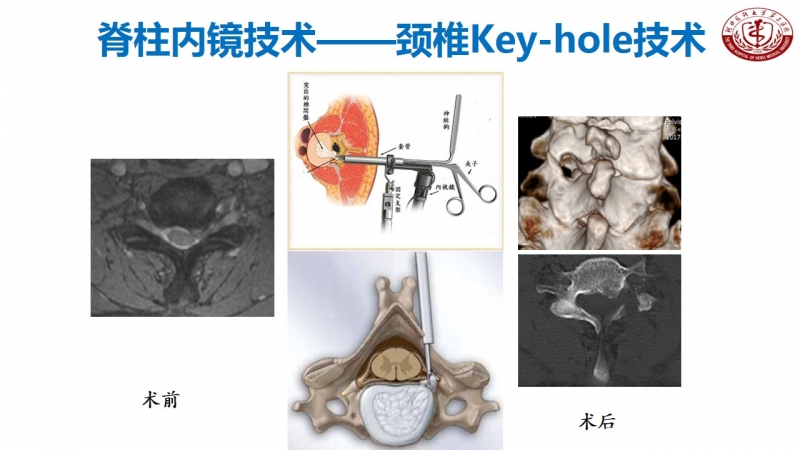

核心技术展示

科室发展,未来可期

作为脊柱外科的主任,丁文元教授时刻不忘科室的建设和发展。目前,河北医科大学第三医院脊柱外科共有33人,其中主任医师9人,副主任医师4人,主治医师11人,分三个病区,共120张床位,年门诊量66000余人次,年手术量4500余台,并开展了一系列脊柱高难手术,如复杂脊柱畸形截骨矫形术、复杂严重颈椎病前后路手术、胸腰椎前后路手术、上颈椎腰骶部复杂手术以及脊柱各种微创手术。

脊柱外科目前所开展的诊疗技术(滑动查看)

相信河北医科大学第三医院脊柱外科在新的学科带头人的领导下,不忘初心,砥砺前行,做好脊柱基础及临床研究,逐步提高学术影响力,攻克临床上各个难关,提升临床诊疗水平,使脊柱外科朝着精准化、微创化、显微化、智能化发展,造福更多患者。